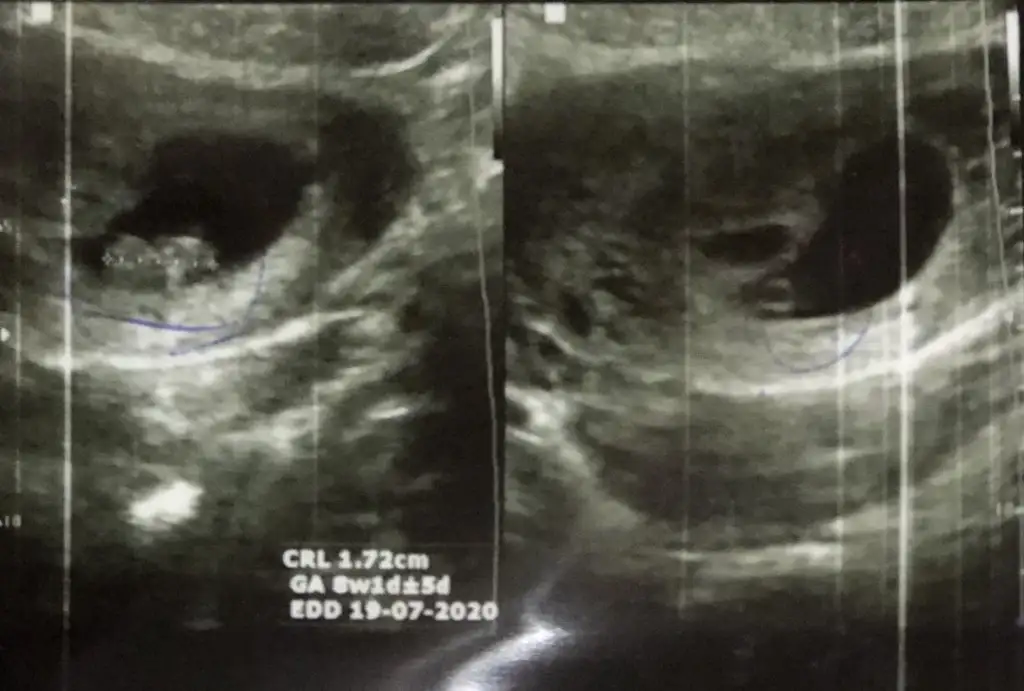

Rica ederim canım benim Hmmm sonradan benimki de muz gibi oldu. İlk attığım fotoğraf 6 haftalık. Bu ise 8Çok sağol canım yok benim ki muz gibi uzundu

Bende pek anlamıyorum da sanırım ilk kese oluşumuna göre dediler burdakiler Rabbim seninde bebeğini sağlıklı bir şekilde kucağına almanı nasip etsin inşallah canımRica ederim canım benim Hmmm sonradan benimki de muz gibi oldu. İlk attığım fotoğraf 6 haftalık. Bu ise 8

Benim de şuan 6 haftalık yuvarlak ama sizinki gibi değişedebikir belkiRica ederim canım benim Hmmm sonradan benimki de muz gibi oldu. İlk attığım fotoğraf 6 haftalık. Bu ise 8